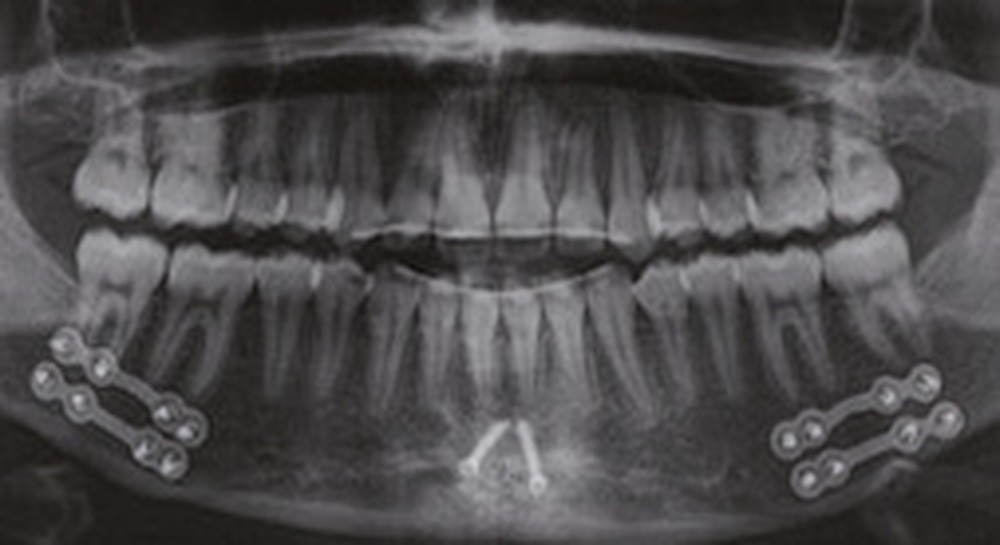

Nous équipons la patiente avec un appareil multi-attaches (.022 x .028 inch pré-informé Roth) mais nous n’avons pas activé l’arcade mandibulaire. La patiente est adressée au chirurgien maxillo-facial (Dr Gonzague Deffrennes, hôpital Beaujon) qui réalise l’avulsion des troisièmes molaires et la pose de plaques vissées avec émergence entre les premières et deuxièmes molaires mandibulaires dans l’axe des brackets (fig. 9). Étant donné l’absence d’encombrement au niveau incisif mandibulaire, nous pouvons rapidement mettre en place les tractions postérieures. Nous solidarisons ainsi le bloc antérieur de canine à canine et réalisons un recul en masse de l’arcade directement des canines aux plaques postérieures. La majeure partie du recul est faite sur un arc acier .018x.025 inch permettant le glissement. La force appliquée est de 250-300 g par côté.

Nous avons pu repositionner l’incisive mandibulaire de 8° (fig. 10), obtenir un surplomb correspondant à la classe II d’Angle et ainsi réaliser l’avancée mandibulaire. Le chirurgien accompagne celle-ci d’une génioplastie afin d’harmoniser le profil. Nous corrigeons la DDD par stripping des incisives mandibulaires ce qui permet de corriger encore de 1° l’axe incisif.